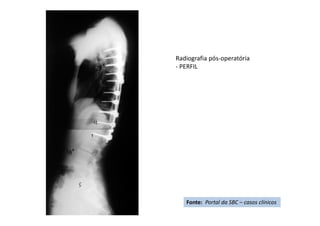

Radiografia pós-operatória

- PERFIL

Fonte: Portal da SBC – casos clínicos

Apresentação de Casos Clínicos

• Escoliose Idiopática do Adolescente

• Resumo do caso: Escoliose idiopática do adolescente tratada

cirurgicamente com artrodese da coluna T4L1 com parafusos

pediculares.

• Paciente (dados): feminino, 13+2 anos, Risser 3, menarca há

9 meses.

• História: Deformidade da coluna percebida pela mãe há 3

meses. Nega tratamento prévio. Nega demais doenças ou uso

de medicações.

• Diagnóstico(s): Escoliose idiopática do adolescente, Lenke

1B-. Tratamento(s): Artrodese da coluna por via posterior T4-

L1 com parafusos pediculares.

• Seguimento ("Follow up"): Seguimento de 2

anos. Literatura:

• Resultado Final: Artrodese seletiva torácica T4-L1, obtida

compensação do tronco e nivelação dos ombros.